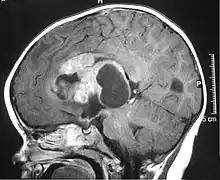

| MRI of an AT/RT | |

Appearance on radiologic exam

AT/RTs can occur at any sites within the CNS; however, about 60% are located in the posterior fossa or cerebellar area. The ASCO study showed 52% posterior fossa; 39% sPNET; 5% pineal; 2% spinal, and 2% multifocal.[3]

The tumors' appearance on CT and MRI are not specific, tending towards large size, calcifications, necrosis (tissue death), and hemorrhage (bleeding). Radiological studies alone cannot identify AT/RT; a pathologist almost always has to evaluate a brain tissue sample.

The increased cellularity of the tumor may make the appearance on an uncontrasted CT to have increased attenuation. Solid parts of the tumor often enhance with contrast MRI finding on T1 and T2 weighted images are variable. Precontrast T2 weighted images may show an isosignal or slightly hypersignal. Solid components of the tumor may enhance with contrast, but not always. MRI studies appear to be more able to pick up metastatic foci in other intracranial locations, as well as intraspinal locations.